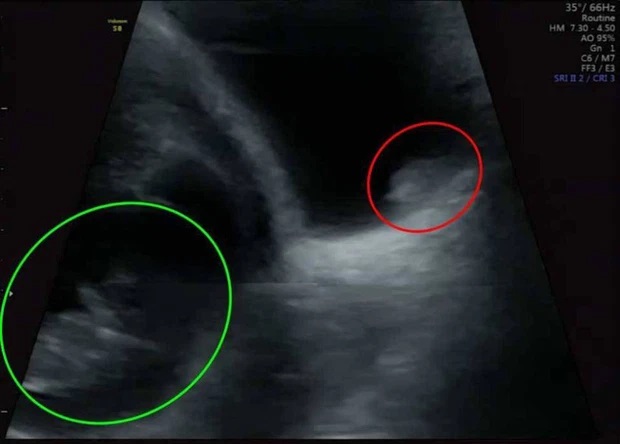

Đi siêu âm thai, bà mẹ Yasmin phát hiện khối u trong bàng quang

Niềm vui ngắn chẳng tày gang, hóa ra "vật thể lạ" đó chính là khối u bàng quang.

"Khi cô ấy thông báo rằng có khối u trong bàng quang, cả 2 vợ chồng tôi đều sốc. Tôi vẫn chưa hình dung được mức độ nghiêm trọng về sức khỏe của mình", Yasmin nói.

Carl nói: "Tôi đã cố trấn an cô ấy rằng không có chuyện gì xảy ra và cả hai chúng tôi đều cố gắng tập trung vào việc có con. Nhưng khi chuyên gia tư vấn nói rằng chắc chắn có một khối u kích thước khoảng 2 centimet ở đó, chúng tôi đã hoàn toàn suy sụp".

48 giờ sau ca phẫu thuật là khoảng thời gian cực quan trọng đối với cặp đôi. Nếu Yasmin bị sảy thai thì có khả năng điều đó sẽ xảy ra trong vài ngày sau ca phẫu thuật. Và may mắn đã mỉm cười với họ, 1 tuần sau đó, khi siêu âm ở tuần thứ 20 tuần, cặp vợ chồng vui mừng khôn xiết vì được thấy con cử động trong bụng Yasmin.